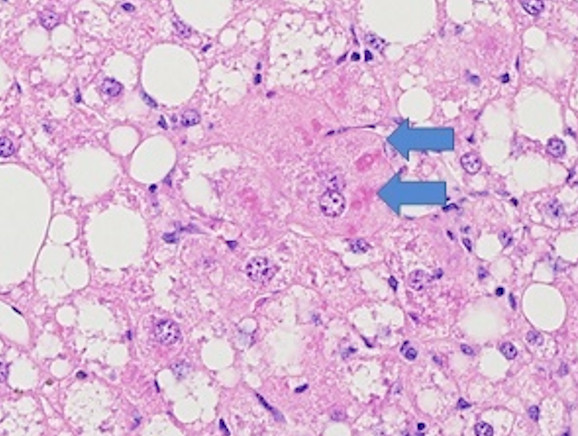

Figure 5: MASH B6 have hepatic crown-like structures (hCLS), a unique histological finding from MASH patients. Hepatic crown-like structures (blue arrowheads) are macrophages surrounding hepatocytes with large lipid vacuoles. Macrophages also form solid inflammatory cell aggregates with other leukocytes (red arrowheads).